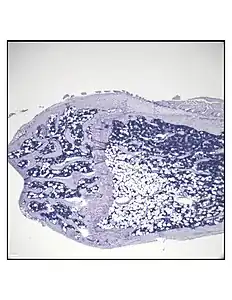

Representative distal femur histologic section of a 16-week-old healthy C57BL/6 mouse demonstrating a typical quantity of marrow adipocytes.

In order to understand the physiology of BMAT, various analytic methods have been applied. BMAds are difficult to isolate and quantify because they are interspersed with bony and hematopoietic elements. Until recently, qualitative measurements of BMAT have relied on bone histology,[51][52] which is subject to site selection bias and cannot adequately quantify the volume of fat in the marrow. Nevertheless, histological techniques and fixation make possible visualization of BMAT, quantification of BMAd size, and BMAT's association with the surrounding endosteum, milieu of cells, and secreted factors.[53][54][55]